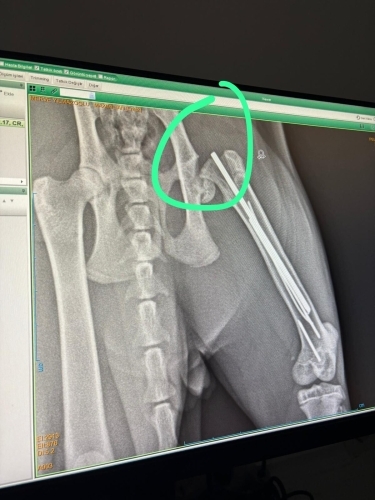

Kedimi sahiplenmeden önce, eski sahibi onu sokakta bacağı kırık şekilde bulmuş. durumu olmadığı için belediyede ameliyat etmişler ve pin takılmış. Biz 4 ay önce sahiplendik, dün pin takılan bacağı tekrar kırıldı çünkü önceki ameliyat berbat yapılmış. Yeni ameliyatta femur başı çıkarıldı, sorunlu pin çıkarıldı. Ancak veteriner hekim biraz olumsuz konuştu sinirler batan pinden zarar gördü bu bacağını kullanır mı kullanmaz mı net konuşmadı 1 ay kafes tedavisi görecek evde ayrıca çok ödem olduğu için kortizon tedavisi gerekebilir. His kaybı yaşamasından ve bacağını kaybetmesinden korkuyorum, aynı durumu yaşayan var mı ?